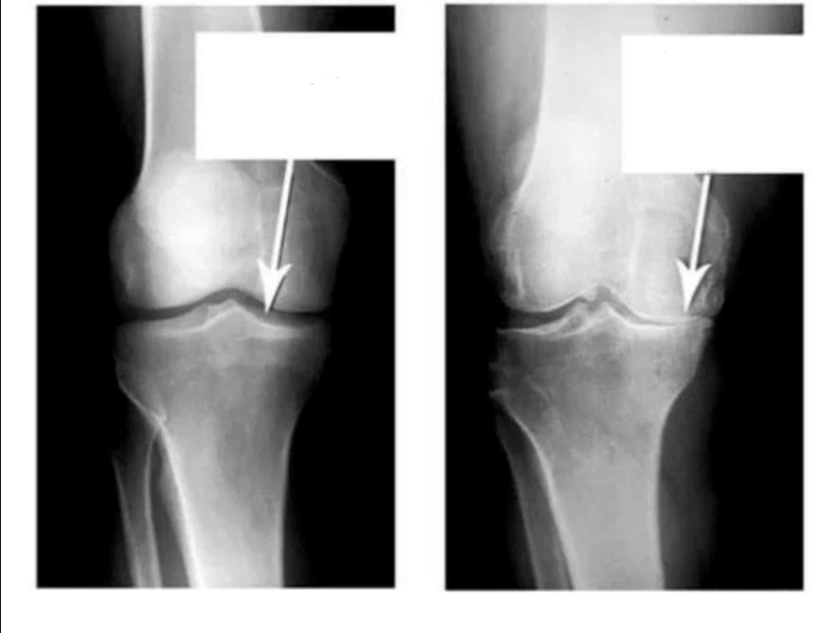

Ба ин суратхо нигаред, мебинед, ки дар расми рост ягон фосилаи бугум вучуд надорад, устухонхо ба хам мемоланд ва боиси дарди сахт мегарданд. Ва боздоштани ин раванд хеле душвор аст! Пас аз чанд сол одам маъюб мешавад ва худро таъмин карда наметавонад.